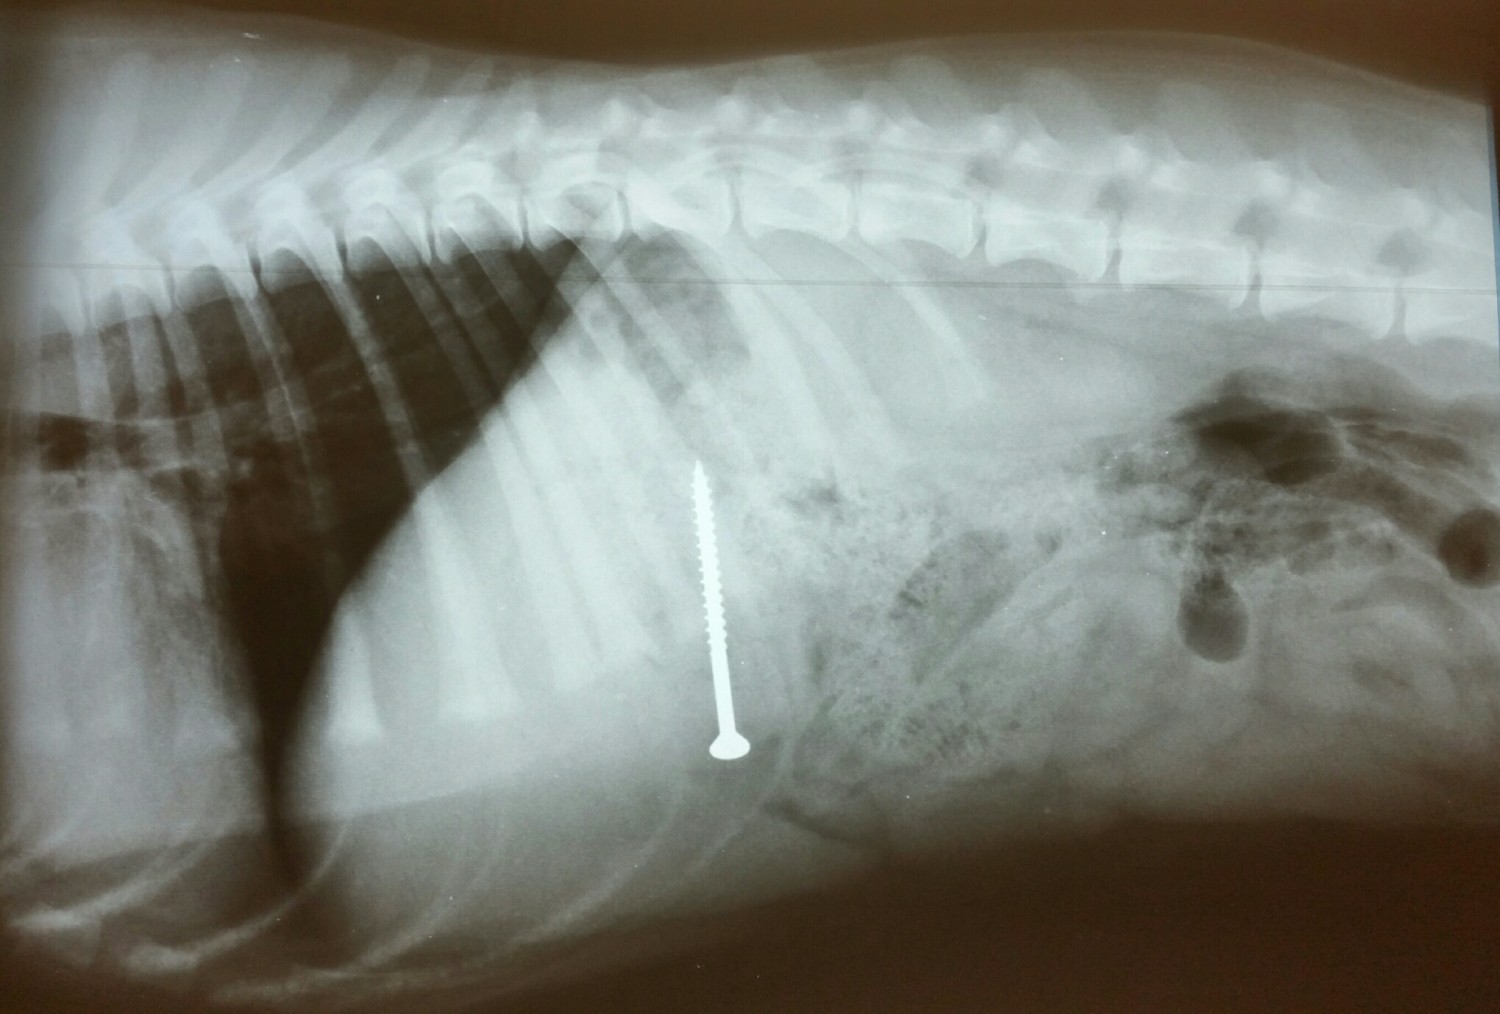

X-Ray

In any medical issue, the first step is an examination by your veterinarian. Sometimes, feeling the abdomen may be enough to diagnose an obstruction. If your veterinarian suspects an intestinal foreign body, he or she will probably recommend x-rays. Though a cloth or plastic object might not be obviously visible, anything metal, rock, or bone will be seen on the x-ray. In a complete obstruction, the radiograph might reveal the tell-tale ballooning intestines at the blockage, similar to the pressurized, tied-off water hose seen in cartoons. Linear obstructive patterns also may be detectable. Despite having clinical signs, however, the intestines may not have enough changes at the time of initial radiographs to diagnose the intestinal blockage. These patients may require repeat x-rays or a contrast study. This may not be an option if the patient is not stable or is actively vomiting. In contrast films, the patient is given a contrast agent to swallow and a series of x-rays are taken over several hours. These monitor whether the contrast material moves through the intestines in a normal period of time, or, if it lingers or even stops at a certain point. Sometimes an ultrasound can also help in finding obstructions in the stomach or intestines. More difficult obstructive cases may not be diagnosed with imaging. Based on the history, symptoms, condition of the patient, and test results, the veterinarian may even recommend an exploratory surgery to find the suspected obstruction.